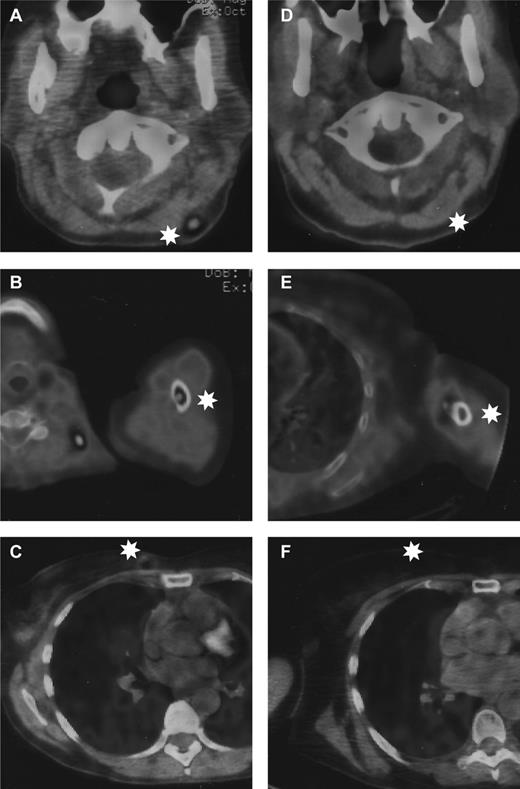

Representative pictures from the positron emission tomography scanner before and after interferon-free anti-HCV treatment. Left panels: photos before antiviral treatment of (A) infiltrated cervical lymph node, (B) left humeral shaft lesion, and (C) right breast lesion. Right panels: photos after sustained virologic response of (D) same cervical area, (E) left humeral shaft, and (F) right breast. White stars indicate the localization of the lymphoma.

Within 2 weeks of treatment, the liver tests returned to normal and HCV RNA was undetectable in the serum. We replaced ribavirin with daclatasvir at week 4 of treatment and conducted a 12-week therapy of sofosbuvir and daclatasvir. Twelve weeks after the end of treatment, HCV RNA remained undetectable in the serum, defining a sustained virologic response. During the course of treatment, we observed a complete clinical and radiologic regression of breast, cervical ganglionic, and humeral shaft lesions, and the patient remained in complete remission 6 months after the end of antiviral treatment (Figure 1).